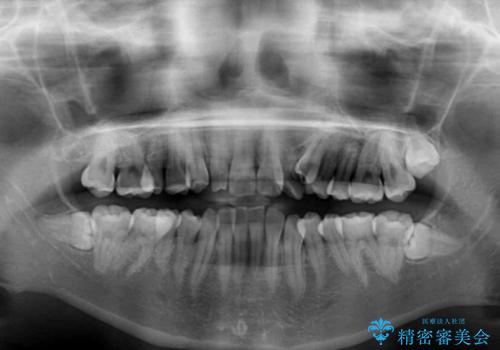

- 八重歯と奥歯の咬み合わせを気にして来院された患者様です。

インビザラインによる矯正治療を希望されたため、八重歯改善のための抜歯矯正部分は補助装置を併用し、その後はインビザラインにて行うこととしました。

下顎の右側変位が顕著であったため、ワイヤー矯正の方が咬み合わせは改善しやすいのですが、ある程度は時間がかかっても良いとのことであったので、インビザラインにて矯正治療を行うこととしました。

骨格的に下顎が右側に変位していたため、上下正中を合わせることは困難であることは分かっていました。それでも、なるべく合わせるようにとしたため、治療期間は長期間となりました。